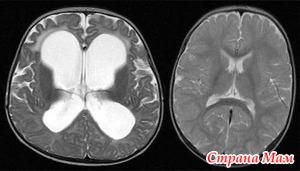

Итак, мы вами продолжаем обсуждение гидроцефалии, поговорим о третьей, само тяжелой степени дисциркуляторной энцефалопатии, типичной для проявлений гидроцефалии. При этом виде энцефалопатии проявления предыдущих стадий усугубляются сильнее. Может наступать развитие слабоумия (деменции), происходит снижение критики, в том числе и самокритики, что не дает адекватно оценивать свое и чужое поведение. При этой стадии энцефалопатии больные практически полностью утрачивают способности к мыслительным процессам. Читать далее»